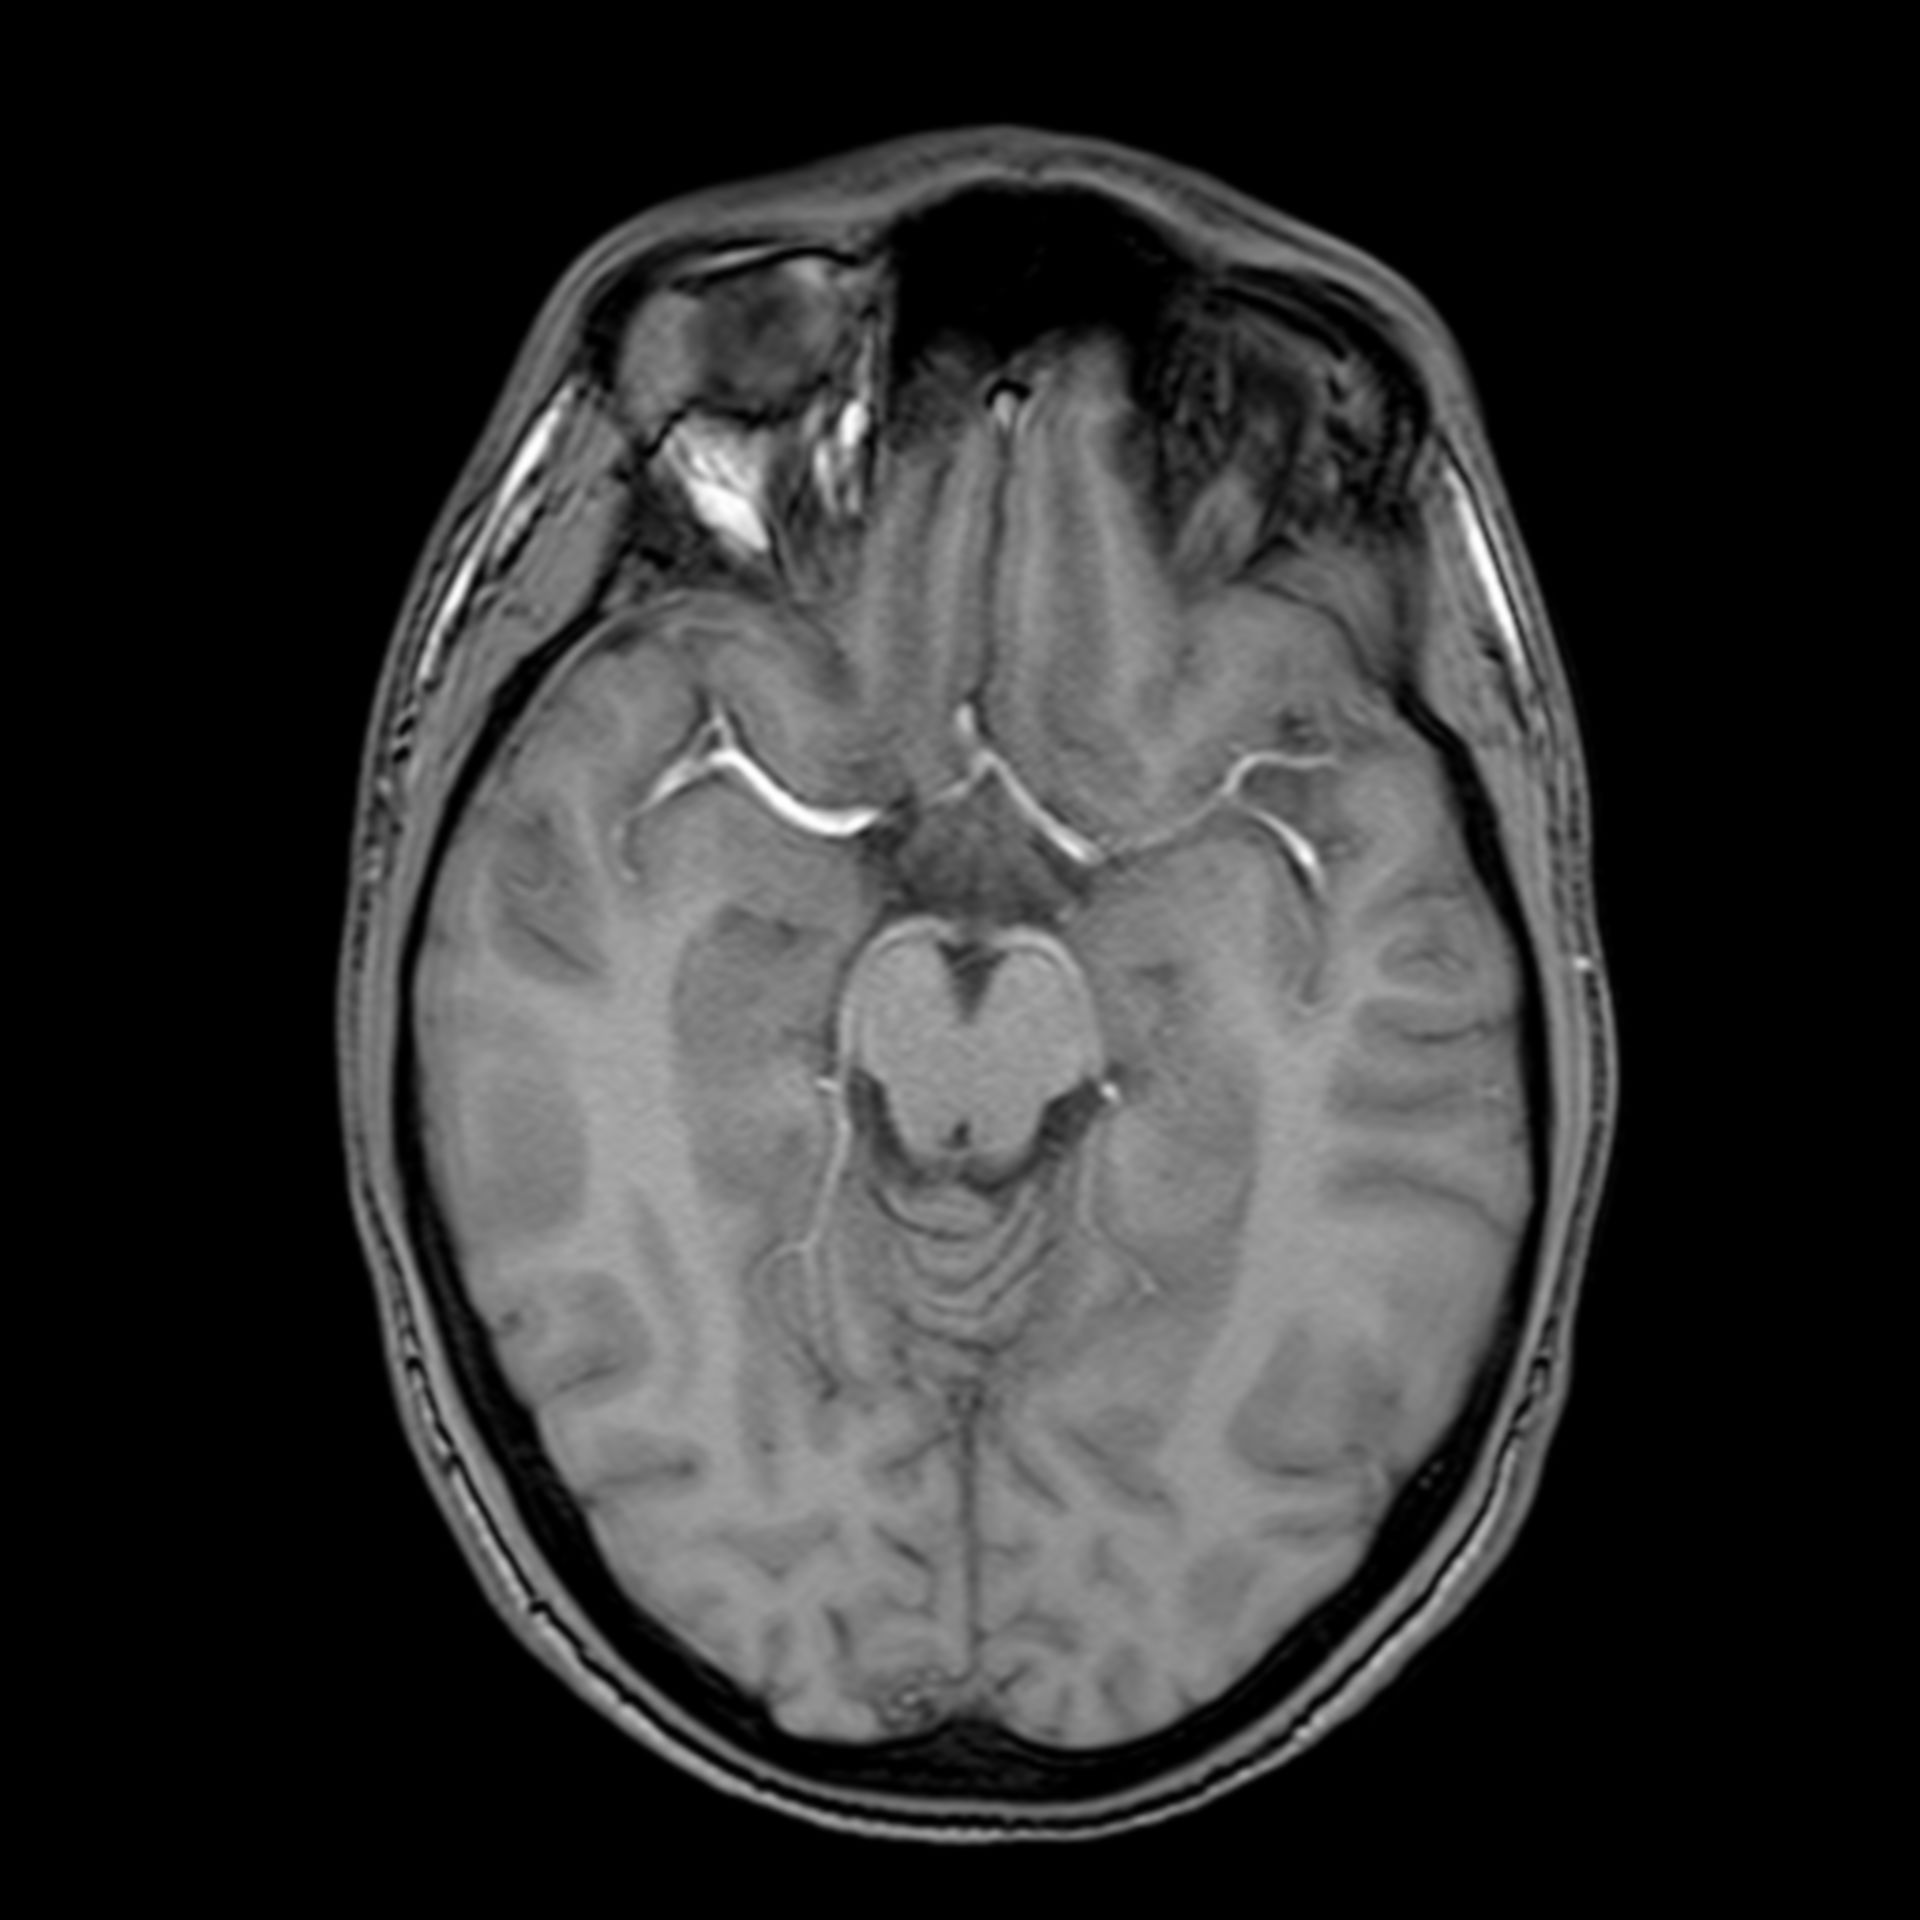

(16/26) MRT Schädel in Transversalebene, T₁‐gewichtet, FFE – DocCheck MRT Knie – DocCheck

(11/26) MRT Schädel in Transversalebene, T₁‐gewichtet, FFE – DocCheck MS Herd MRT (1) – DocCheck